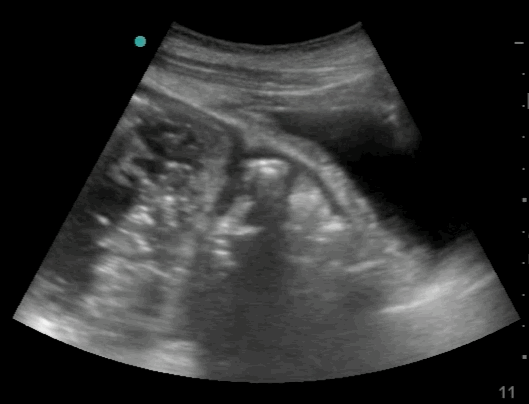

20_Abdomen_RUQ_Perihepatic

Free fluid – Hepatico-Diaphragmatic recess